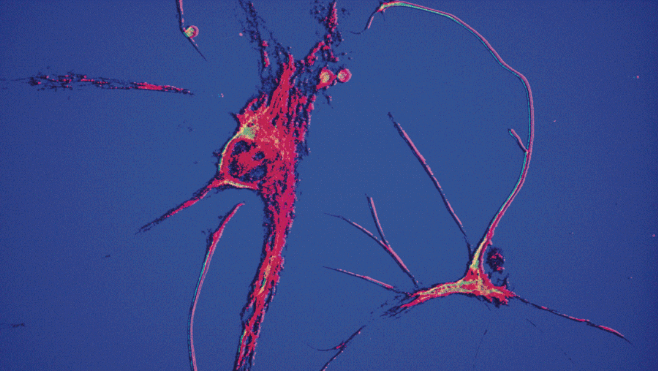

生物顯微成像案例

我們的顯微成像方案,結(jié)構(gòu)和功能各不相同,但核心都是一致的,即模塊化的集成搭建原則、出色穩(wěn)定的光學(xué)成像質(zhì)量。